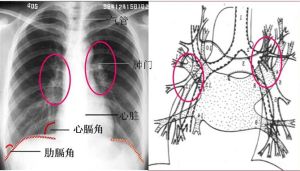

膈肌疾病的診斷和治療 主要依靠X射線對胸部﹑膈肌本身或胃﹑腸的詳細檢查。膈疝與膈膨出一般不難鑑別﹐膈膨出病例的膈肌完整﹐仍在升高的腹腔內臟之上。疑診的膈膨出或腫瘤等可作人工氣腹(將消毒空氣直接注入腹腔)後的X射線檢查﹐鑑別膈上﹑下及膈肌本身病變。疑難病例可作CT檢查。

主要依靠X射線對胸部﹑膈肌本身或胃﹑腸的詳細檢查。膈疝與膈膨出一般不難鑑別﹐膈膨出病例的膈肌完整﹐仍在升高的腹腔內臟之上。疑診的膈膨出或腫瘤等可作人工氣腹(將消毒空氣直接注入腹腔)後的X射線檢查﹐鑑別膈上﹑下及膈肌本身病變。疑難病例可作CT檢查。膈肌疾病的治療主要是外科手術。